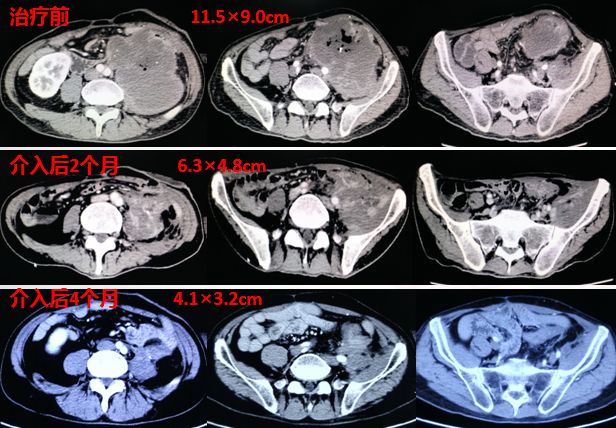

介入治疗前腹腔肿块巨大,>10厘米

介入治疗取得明显疗效:

患者症状改善明显:

疼痛缓解

腹部包块已触及不到

体重增加40斤